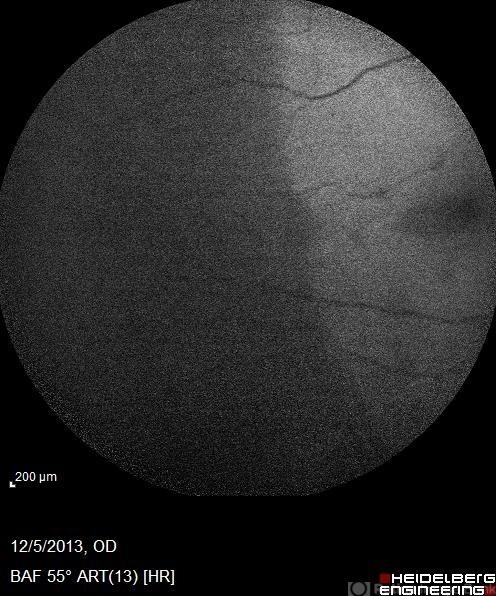

- AZOOR

- Condition/keywords

- acute zonal occult outer retinopathy (AZOOR), autofluorescence imaging

- AF 12-5-16